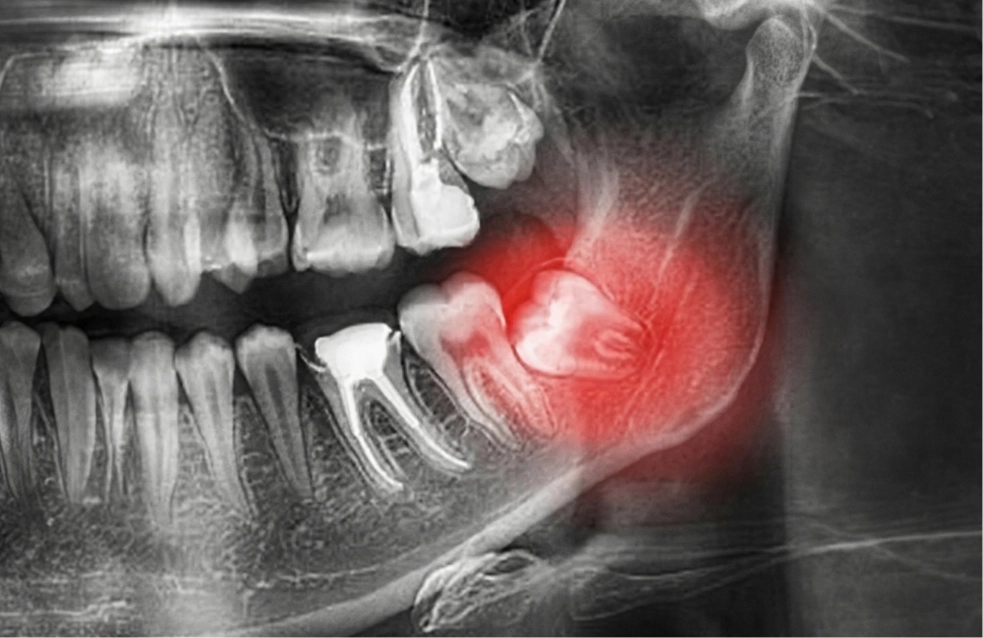

• Cirugía de terceros molares (muelas del juicio)